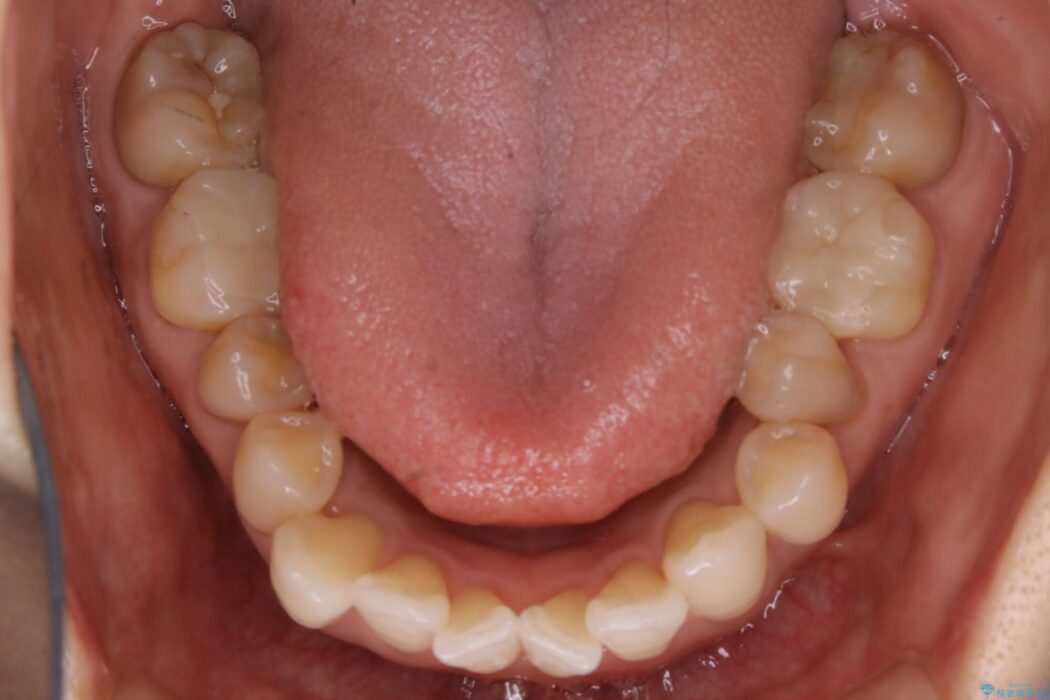

全体的に歯列が狭窄しており、本来外側に覆いかぶさっている上の前歯が内側に入り込んでいました。

歯並びが悪くなる原因の一つに「歯列弓の狭窄」というものがあります。

奥歯や前歯が内側(舌側)に倒れ込んでしまったり、歯が生えてくる位置が内側になってしまうことにより歯並びのアーチが狭くなってしまうことを言います。

このような場合、歯並びのアーチを拡大してあげるだけでもガタつきを無くすためのスペースがかなり作れることがあります。